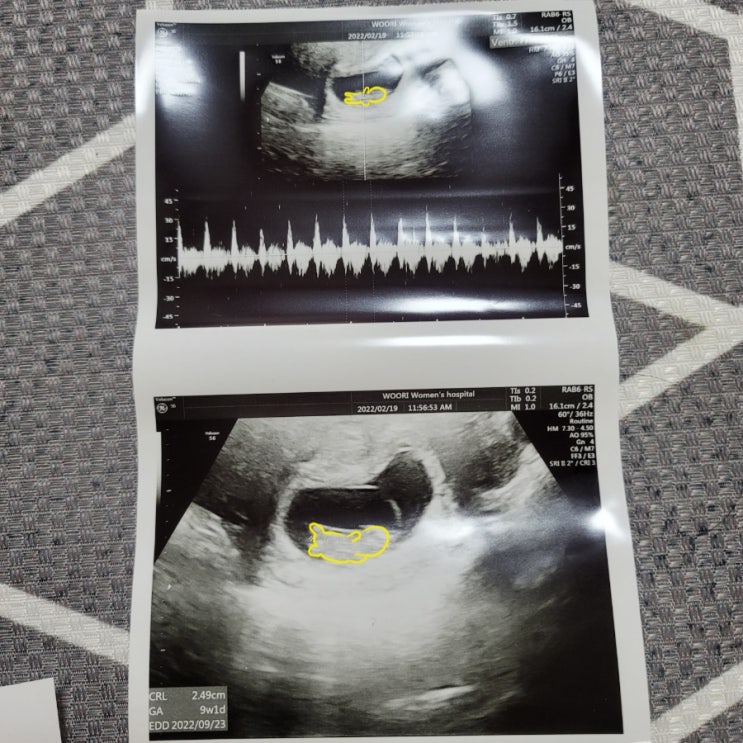

[임신9주2일]

ㅋㅋㅋㅋㅋㅋㅋㅋ임신9주차❣️ 심장소리도 더커지고 빨라진 우리또복이?? 이제 팔다리가 나와서 꼬...